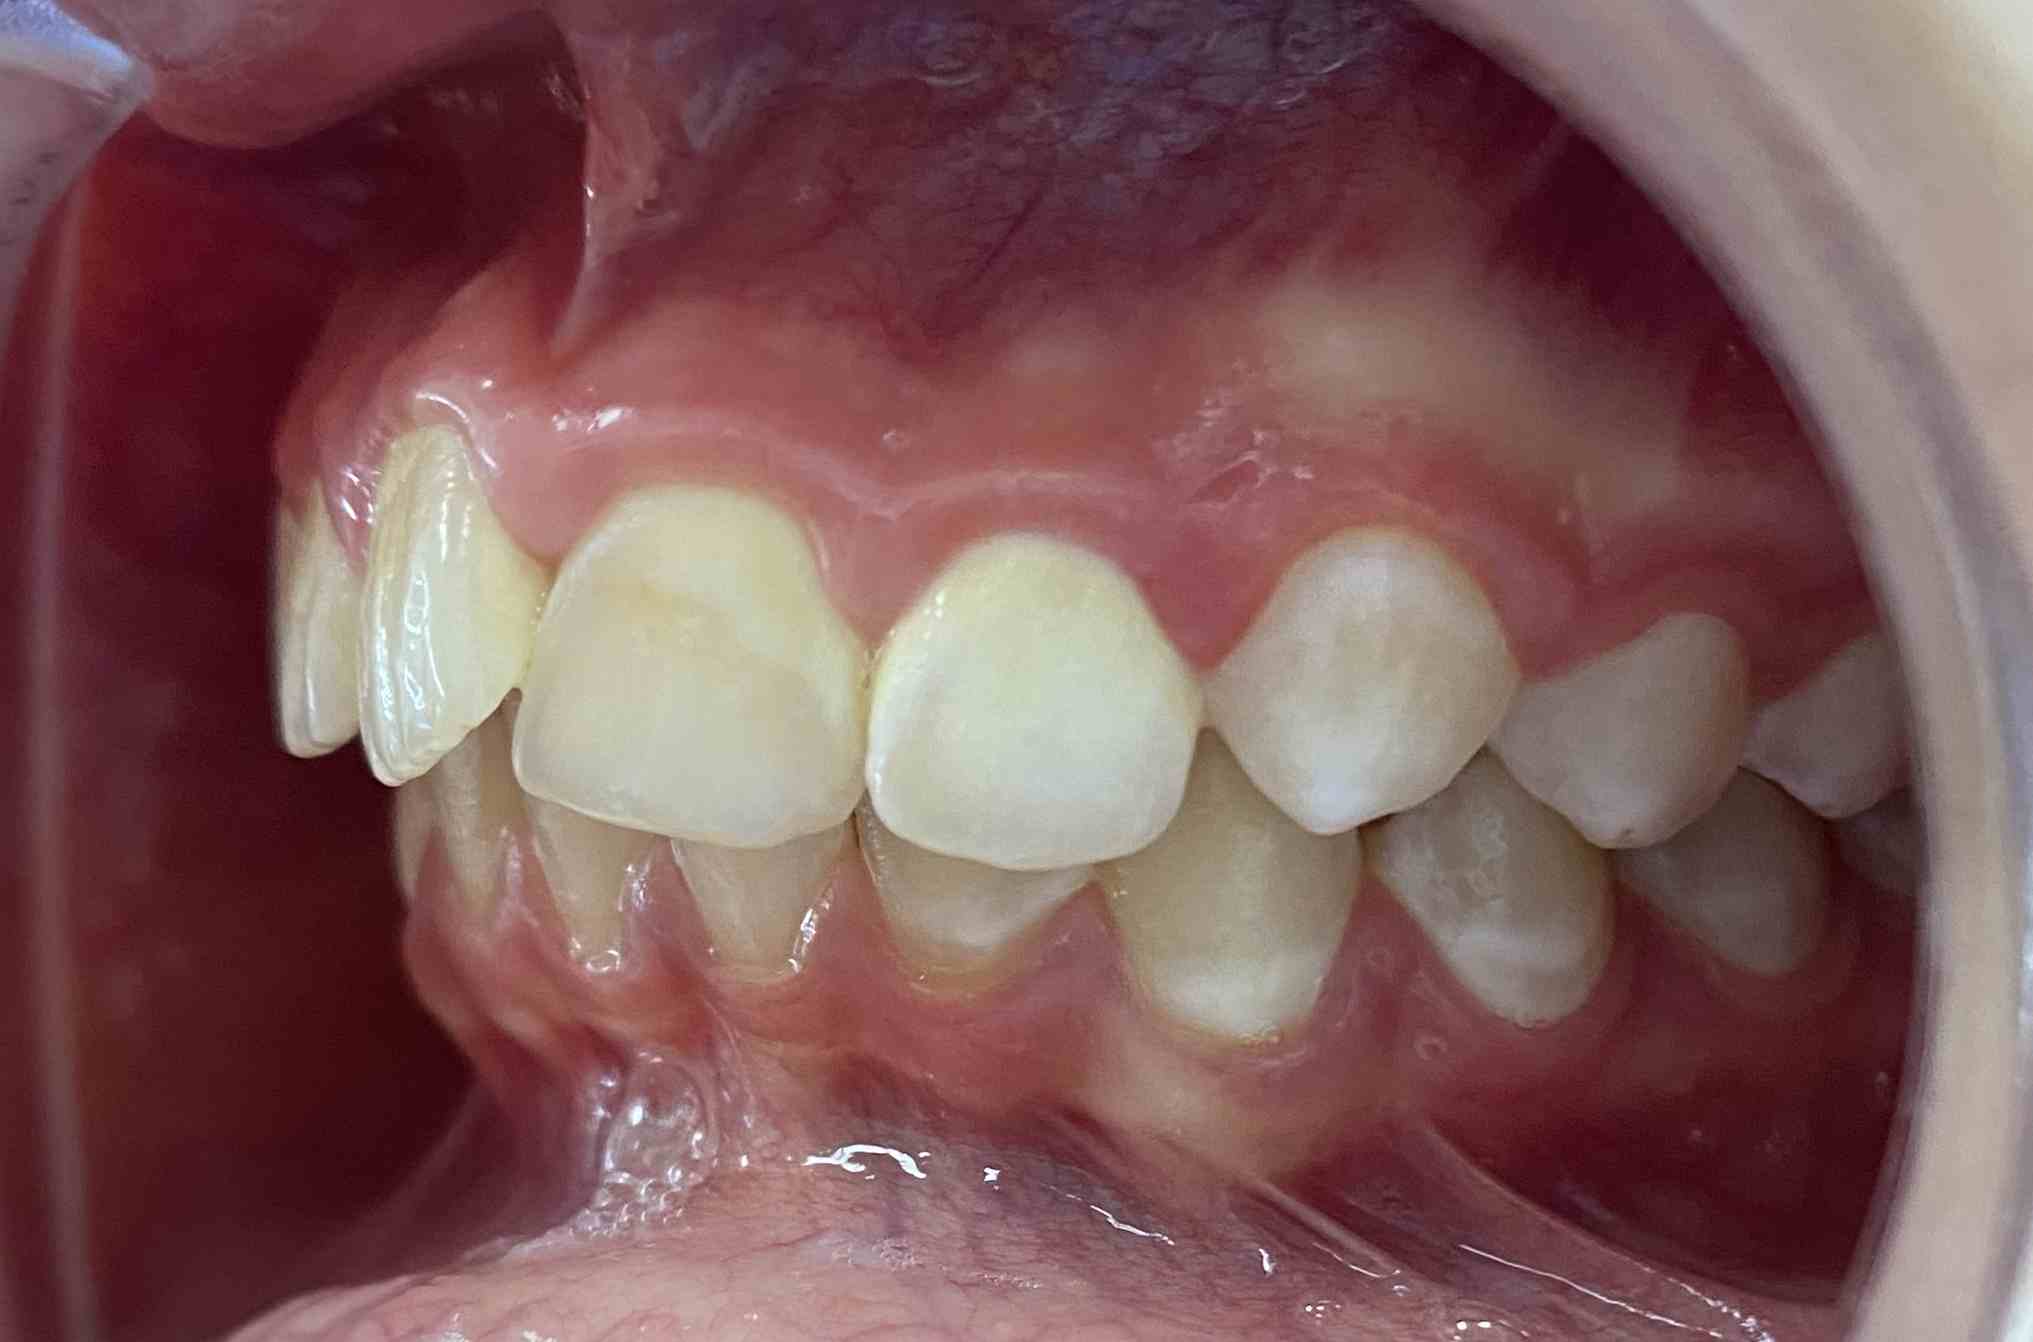

Pic.16. Mesial position of tooth 11 with lack of space in the dental arch.